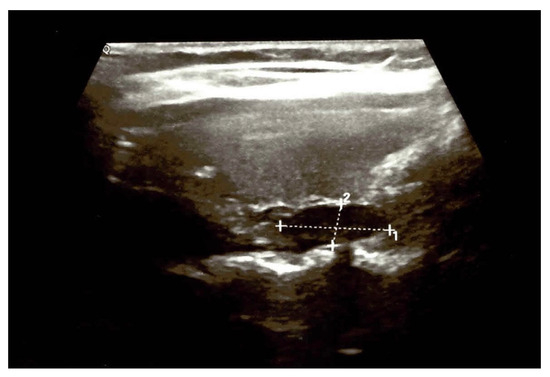

3. Clinical Vignette